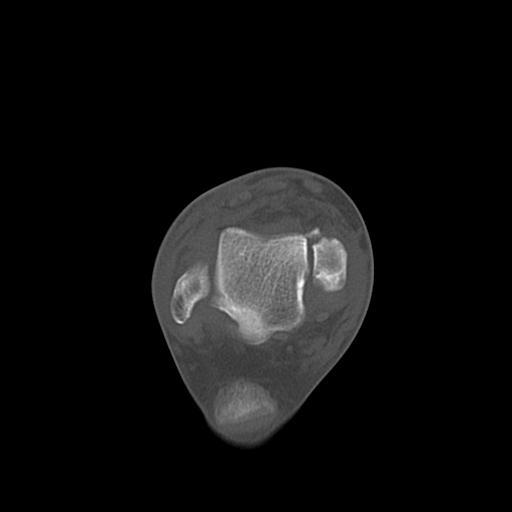

102755 1/4 2R 1/15 2R 右足関節 68歳女性 右三果脱臼骨折